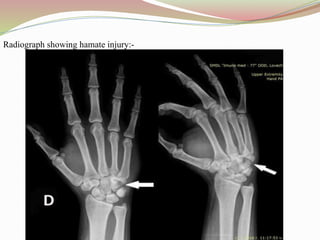

Radiograph showing hamate injury:-